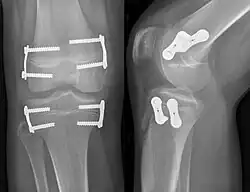

- Zweilochplatte: Die modifizierte Plattenosteosynthese wird unter Röntgenkontrolle quer über die Wachstumsfuge eingebracht und an beiden Seiten der Fuge mit je einer Schraube fixiert. Dadurch wirkt die außen auf dem Periost aufliegende Platte wie eine Zuggurtung. Wie bei den Blount-Klammern kommt es durch Kompression der Wachstumsfuge zu einem Wachstumsstillstand im Bereich der Plattenosteosynthese.

Dieses Verfahren wurde erstmals 2006 von dem US-Amerikaner P. M. Stevens vorgestellt, er entwickelte die als Eight-plate bekannte und patentrechtlich geschützte erste spezielle Titan-Zweilochplatte ohne winkelstabile 4,5-mm-Schraubenverankerung für die Firma Orthofix. In den Folgejahren wurden mehrere Konkurrenzprodukte nach demselben Prinzip auf den Markt gebracht, teilweise sind die Schrauben winkelstabil verankert, teilweise nicht, z. B. PediPlate. Diese Technik hat sich binnen weniger Jahre durchgesetzt und wird inzwischen am häufigsten angewandt.

Erste Studien bei X-Beinen und O-Beinen sind erfolgversprechend und zeigen vergleichbare bis bessere Ergebnisse gegenüber den anderen Verfahren.[7] In einer Übersicht der publizierten Artikel zu Achsabweichungen in der Frontalebene, also X- und O-Beinen, wurden in 87,6 % die gewünschte Korrektur erreicht. Bei Epiphyseodesen zur Behandlung des Morbus Blount, zur Behandlung von Fehlstellungen bei teilweise geschlossenen Wachstumsfugen, sowie bei übergewichtigen Kindern sind die Ergebnisse jedoch nicht überzeugend.[8]

Als Komplikationen wurden wie bei den anderen Verfahren Schraubenbrüche sowie ein Rebound-Phänomen nach Plattenentfernung beschrieben.